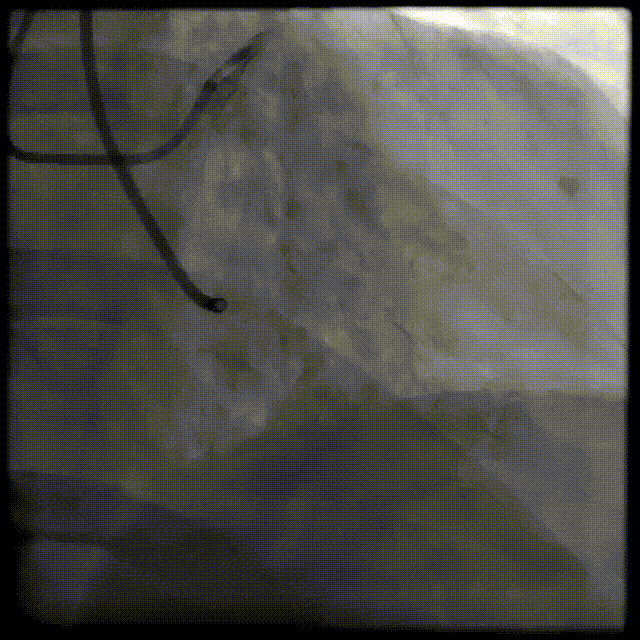

A.优先考虑桡动脉入路;

B.分次手术,先干预LCX,再考虑开通RCA,必要时逆向,经间隔支CC;

右冠开口异常指引导管选择

基于以下考虑:

经桡入路,优先6F;

易操作,易到位,安全性高;

对于低位开口且近段上翘的右冠,可以考虑选用JL3.5/JL4指引导管,也可以使用JR3.5/JR4深插来实现良好的同轴及支撑;

右冠CTO病变需要使用7F导管,提升支撑性。

最终选择:

RCA:7FJL4 GC LCA:6FJL4型号